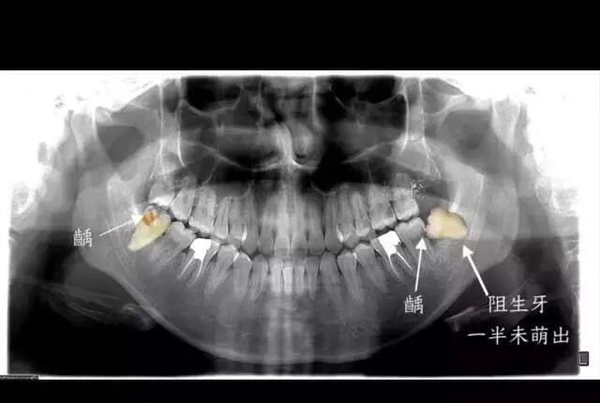

但实际上智齿和智商,除了都姓智,完全没关系。尽管有些人的智齿从来没痛过,但是有可能还是要拔。先给大家看一张照片。这些就是在本人这段时间手底下被拔的相对完整的智齿,而更多的智齿其实已经在拔牙过程中四分五裂。即便如此,这些幸存下来的智齿,或多或少也已经出现了各种龋损和破坏。

虽然说大多数被拔的智齿都或多或少会引起、或曾经引起疼痛,但痛或不痛真不是医生确定智齿要不要拔除的根本原因。拔牙的原因很多,但是最简单的一种判断方式就是,这个智齿是否长得足够正。言下之意就是,尽管暂时还没有引起疼痛,那些长歪的智齿也是越早拔除越好。

原因就在于长歪的智齿非常不容易清洁,食物常常会残留,有的就会导致智齿及周围组织疼痛,更严重的是,它还会导致智齿前方的磨牙出现蛀牙,进一步则出现牙痛,最严重的、也非常常见的状况是,智齿要拔掉先不说,连同智齿前方的第二磨牙都出现不可挽救的龋坏,只能一起拔掉。

不过话说回来,也有一些特别“乖巧”的智齿,整整齐齐长出来,上下可以完美咬合,也没有什么蛀牙,平时都能刷干净。那么这种“优秀、听话”的智齿完全可以留下,成为我们咀嚼食物的工具。除了这些健康的智齿可以不拔,还有一些智齿深深埋在骨头里,而且完全没有萌出到口腔的迹象,那么也可以先不拔。但是要保持观察,一有动静,还是要防范!